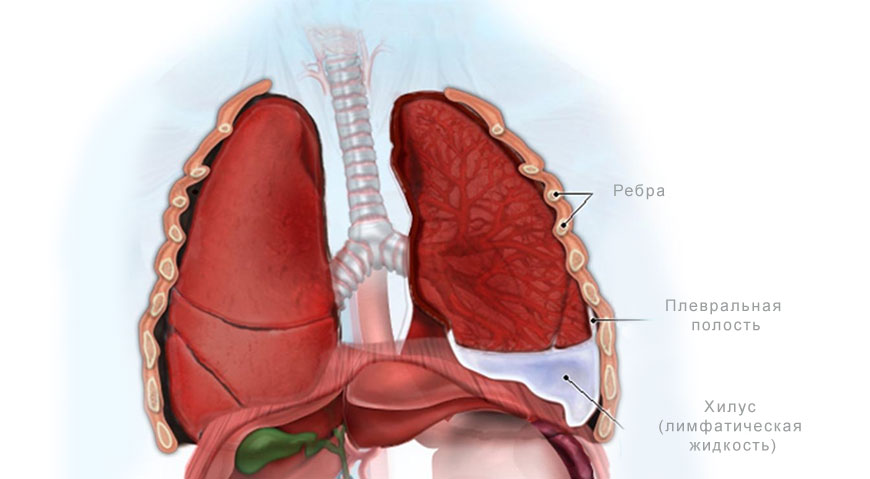

Диагностика плеврального выпота: что нужно знать